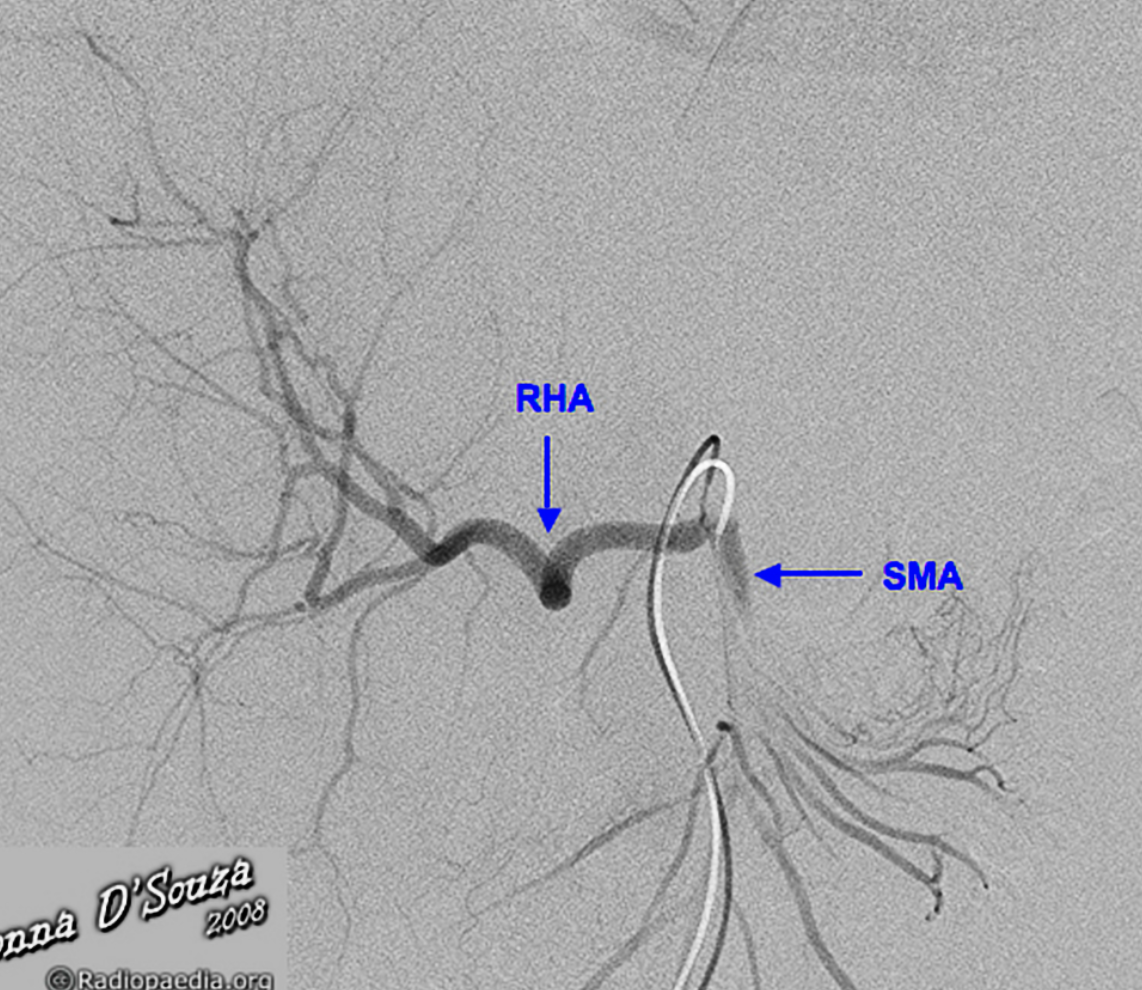

What is this sign and condition?

Replaced right hepatic artery (RHA) arising from the superior mesenteric artery (SMA).

Case Discussion

The right hepatic artery arises from the superior mesenteric artery (SMA), also referred to as “replaced to the SMA”, in 9 to 15% of the population. It is the most common variant in hepatic arterial anatomy.

Core tip: Appreciation and study of hepatic arterial anatomical variability is essential to the successful performance of complex pancreaticobiliary procedures. An aberrant right hepatic artery (aRHA) represents the vascular anomaly encountered most frequently during pancreatoduodenectomy (PD) and, because of its course, is most susceptible to intraoperative damage and tumor involvement. When an aRHA is present, the challenge in peripancreatic malignant disease is to balance its preservation and the need to achieve oncological clearance. In this study, we analyzed the incidence of aRHA and its relationship with the operative complexity, occurrence of complications and oncological clearance in a large cohort of patients undergoing PD.

An aRHA represents the vascular anomaly encountered most frequently during PD. It may have a suprapancreatic, intrapancreatic or rarely transpancreatic course, and, because of its course, it is most susceptible to intraoperative damage and tumor involvement[4,5]. The incidence of an aRHA identified in patients undergoing PD varies from 11%-26.5%[1,6]. When an aRHA is present, the challenge in peripancreatic malignant disease is to balance between its preservation and the need to achieve oncological clearance, which represents the only chance for prolonged survival[1,5,7]. The presence of an aRHA leads not only to an alteration in the surgical approach, but may also adversely affect the outcomes of the surgical procedure[5,8]. In this study, we analyzed the incidence of aRHA and its relationship with the operative complexity, occurrence of complications and oncological clearance in a large cohort of patients undergoing PD.